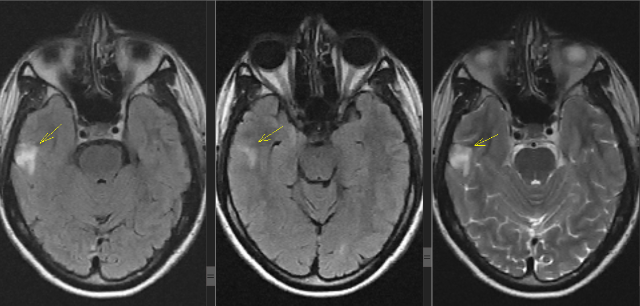

Есть очаги в головном мозге